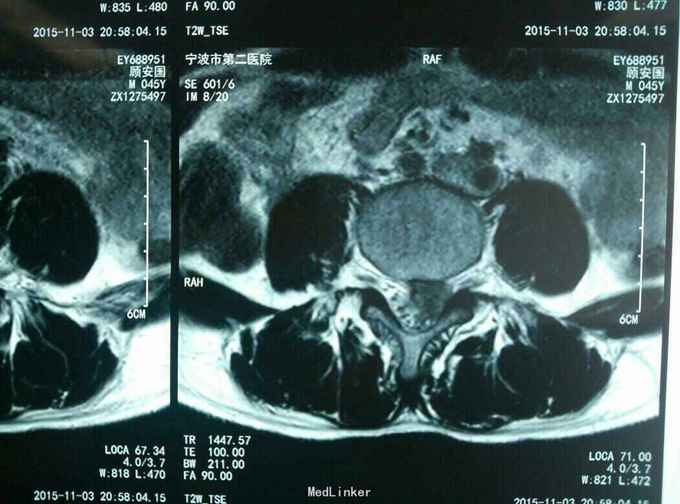

查体:L45间隙压痛,左侧小腿外侧及左足拇趾感觉减退,左下肢肌力四级,左侧下肢直腿抬高试验30度阳性。腰椎MR提示: L4/5椎间盘脱出向上高度游离,压迫左侧神经根。

诊断:L45腰椎间盘脱出游离。 治疗:行侧路椎间孔镜手术。